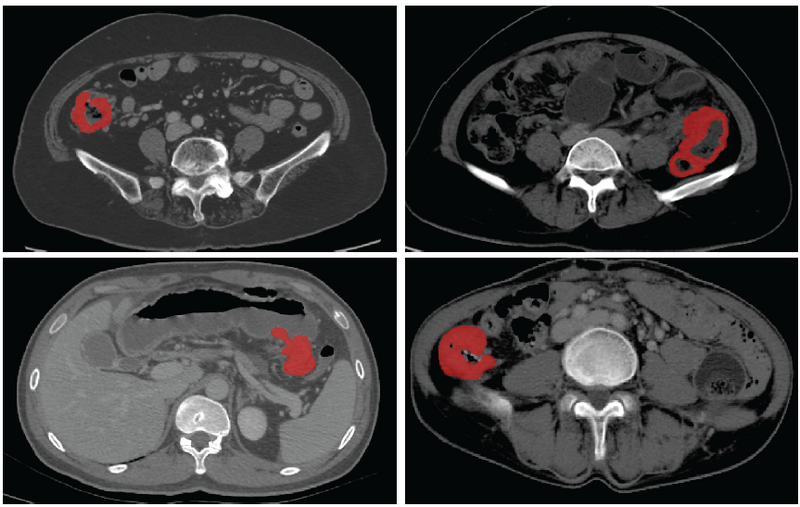

基于CT影像的结肠癌病灶分割

据介绍,基于医学影像的人工智能为肠癌个体化诊疗提供了巨大的可能性,已经有多项研究实现了病人的疗效预测、术后复发风险评估,但这些应用无不依赖于精准的病灶分割。此次SOUSA技术的开发在国际上首次实现了结肠癌的自动分割,为加速肠癌人工智能精准诊疗的临床应用奠定了基础。自动化标准化的精准影像信息处理将有效地降低经济、时间和人力成本,为精准诊疗的实施提供了重要的临床依据,具备极大的临床转化应用前景。

团队利用来自bat365在线中国登录入口附属第六医院和喀地一院的923例有标注结肠癌CT影像和2670例无标注结肠癌CT影像作为SOUSA框架的训练数据集,并利用417例结肠癌CT影像对SOUSA框架进行验证,结果显示其自动分割效果优于现有的弱监督和半监督学习模型。与目前最先进的方法ICT (Verma et al.,2019)、不确定性感知(Yu et al.,2019)和自我训练相比,SOUSA框架在每个数据比率上都达到了最佳性能。此外,当数据集的大小有限时,SOUSA框架的性能甚至与使用密集注释的模型的性能相当。

对肠癌数据集使用不同方法的自动分割结果